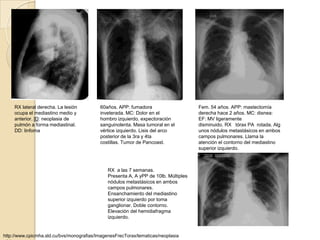

RX lateral derecha. La lesión         60años. APP: fumadora                      Fem. 54 años. APP: mastectomía

ocupa el mediastino medio y           inveterada. MC: Dolor en el                derecha hace 2 años. MC: disnea:

anterior. ID: neoplasia de            hombro izquierdo, expectoración            EF: MV ligeramente

pulmón a forma mediastinal.           sanguinolenta. Masa tumoral en el          disminuido. RX tórax PA rotada. Alg

DD: linfoma                           vértice izquierdo. Lisis del arco          unos nódulos metastásicos en ambos

posterior de la 3ra y 4ta                  campos pulmonares. Llama la

costillas. Tumor de Pancoast.              atención el contorno del mediastino

superior izquierdo.

RX a las 7 semanas.

Presenta A, A yPP de 10lb. Múltiples

nódulos metastásicos en ambos

campos pulmonares.

Ensanchamiento del mediastino

superior izquierdo por toma

ganglionar. Doble contorno.

Elevación del hemidiafragma

izquierdo.